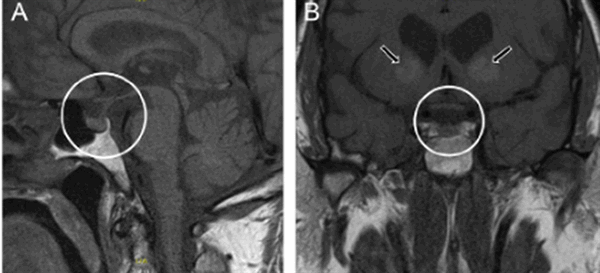

МРТ гипофиза с контрастом и без: А- гипофиз нормальных размеров (обведено кругом), В - симметричные кальцификации (стрелки)

Вопрос что лучше сделать: “МРТ гипофиза с контрастом или без?” - должен решить врач. Последний порекомендует приемлемые для получения качественных изображений характеристики аппарата: сканы, сделанные с помощью низкопольных аппаратах с открытым контуром малоинформативны. Оптимально пройти обследование на томографе с мощностью от 1,5 Тесла.

Учитывая размер гипофиза (с горошину), МРТ преимущественно выполняют с введением контрастного вещества. В качестве красителя используют растворимые соли (хелаты) гадолиния, которые не представляют опасности для организма и при накоплении тканями обеспечивают лучшую визуализацию. Побочные эффекты встречаются менее, чем у 1% людей. Контрастирование ограничивают: